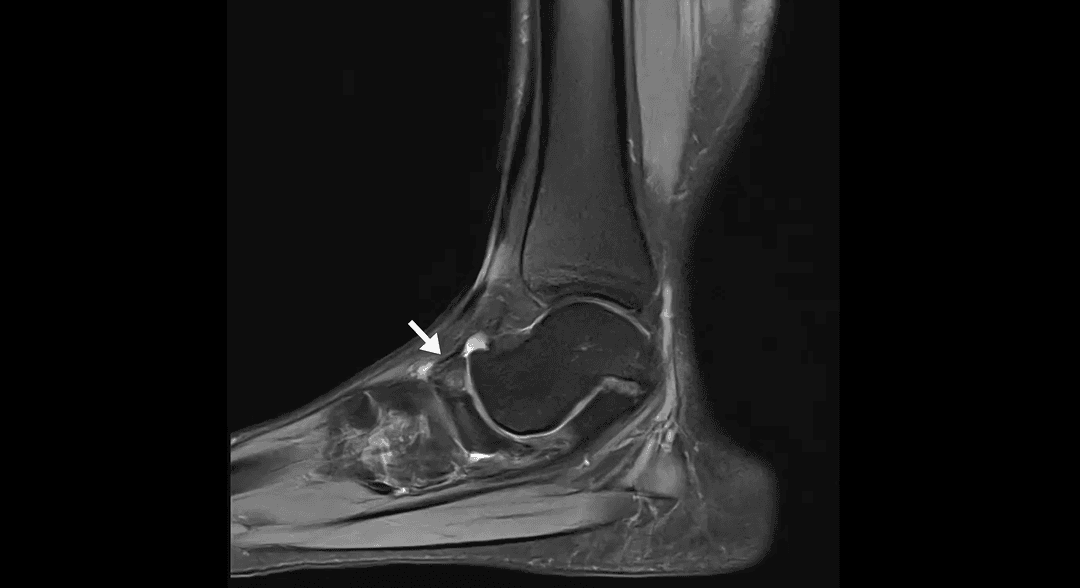

IRM

Description

La maladie de Köhler est une ostéochondrose rare affectant l'os naviculaire du pied chez les enfants. Elle est caractérisée par une nécrose avasculaire transitoire de cet os, conduisant à des douleurs et à des difficultés à marcher. La maladie survient généralement chez les enfants âgés de 3 à 7 ans, avec une prédominance chez les garçons.